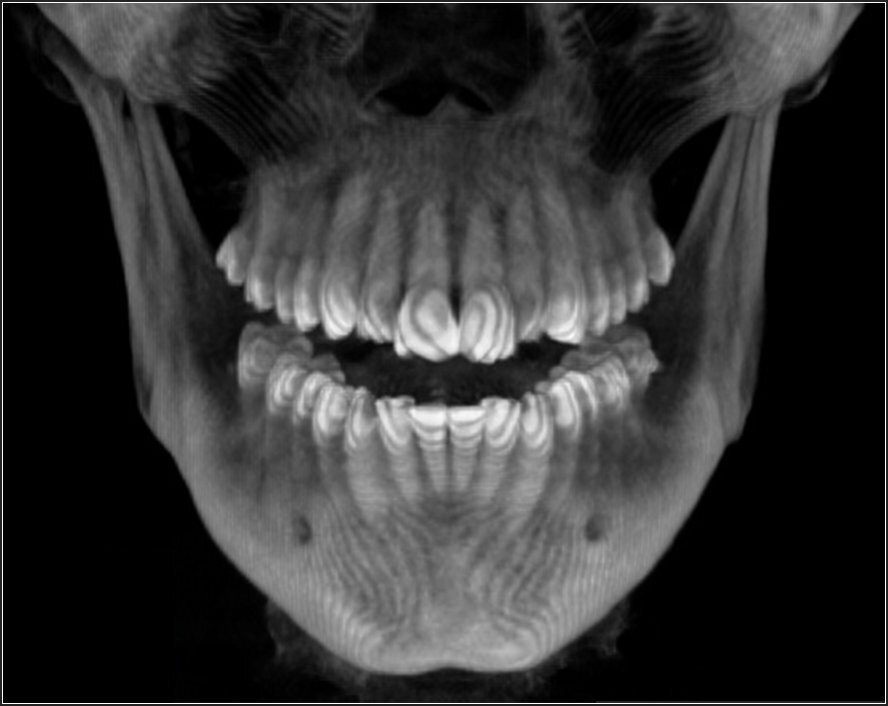

Each patient underwent a medical and dental history, a comprehensive clinical examination, standardized 3D-CBCT imaging, (Figure 1 & Figure 2) to confirm TMJs were stable and well adapted.